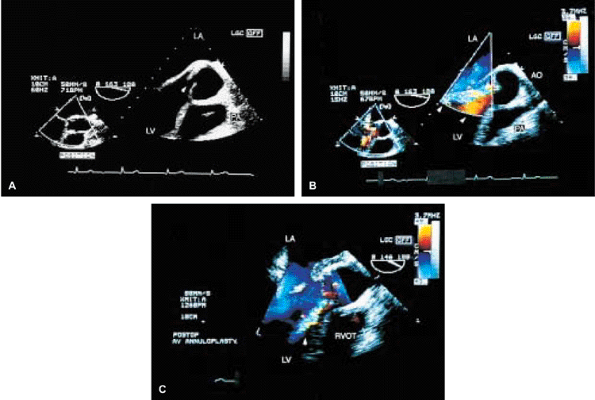

FIGURE 5.50. Aortic valve annuloplasty. This patient presented with severe prolapse and noncoaptation (arrow in A) of the aortic valve leaflets, resulting in severe aortic regurgitation (AR) (arrowheads in B). Following aortic valve annuloplasty, AR is reduced and now is only mild (arrow in C). AO, aorta; LA, left atrium; LV, left ventricle; PA, pulmonary artery; RVOT, right ventricular outflow tract. |